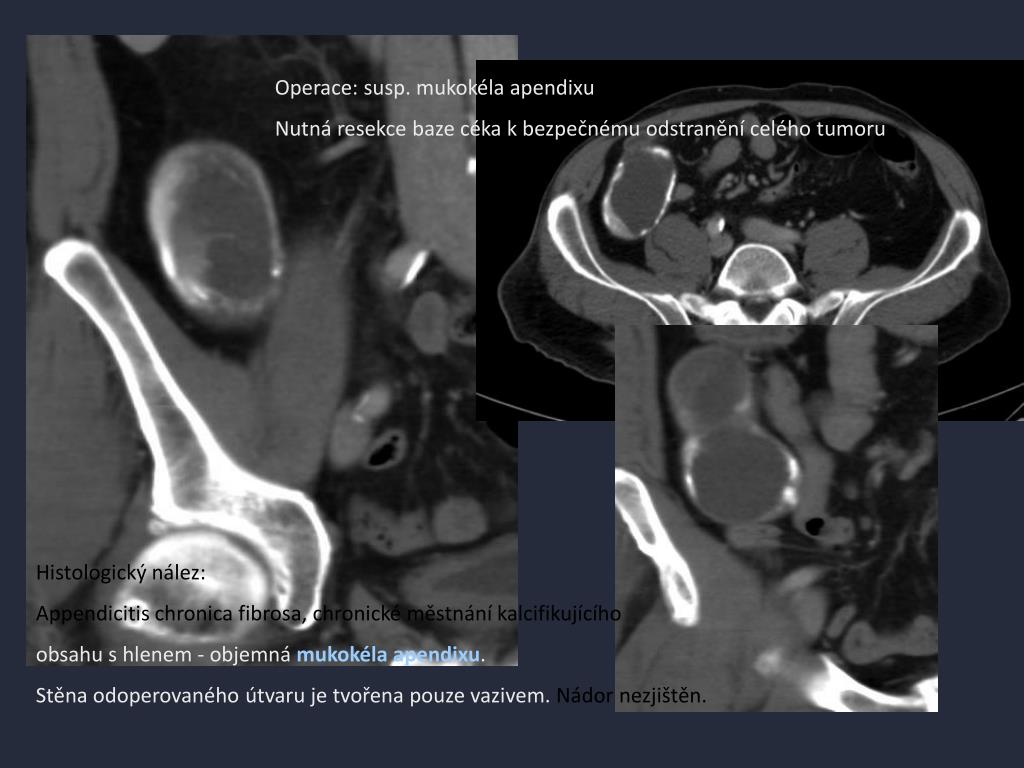

14. Operace: susp. mukokéla apendixu Nutná resekce baze céka k bezpečnému odstranění celého tumoru Histologický nález: Appendicitis chronica fibrosa, chronické městnání kalcifikujícího obsahu s hlenem - objemná mukokéla apendixu. Stěna odoperovaného útvaru je tvořena pouze vazivem. Nádor nezjištěn.

15. Mucocele apendixu Lumen apendixu distendované mucinózním obsahem. • různé histopatologické jednotky - fokální nebo difúzní hyperplazii sliznice, mucinózní cystadenom a mucinózní cystadenokarcinom. • Ruptura mucocele může vést ke vzniku tzv. pseudomyxoma peritonei. • Vzácný nález - 0,25 % appendektomií. • U žen je asi čtyřikrát častější než u mužů, průměrný věk 55 let. • Bolest v pravém hypogastriu, často asymptomatické. • Maligní potenciál - preoperativní diagnóza vede k odlišným chirurgickým technikám !